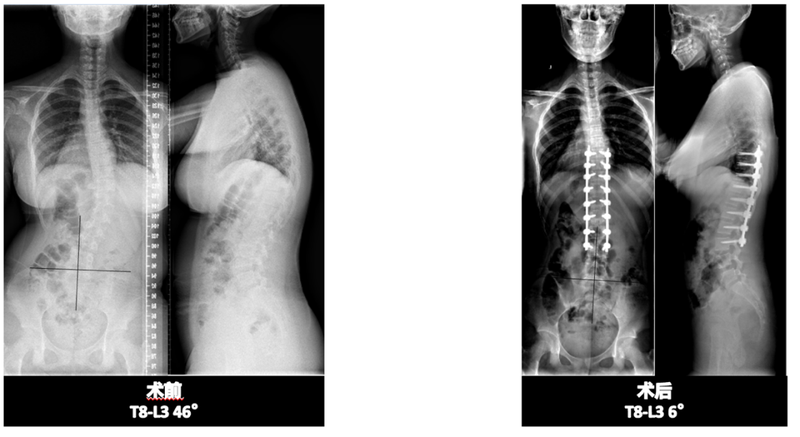

日常工作-2例青少年特發(fā)性脊柱側(cè)凸患者手術(shù)

近幾年脊柱側(cè)凸比例逐年增加,上升之快已成為繼近視、肥胖后危害青少年健康的“第三大殺手”。往往近視和肥胖,父母會早期覺察,而且中小學(xué)生每年查體中也都會常規(guī)體檢,早發(fā)現(xiàn)后也會早期及時干預(yù)。北京協(xié)和醫(yī)院骨科在手術(shù)治療青少年特發(fā)性脊柱側(cè)凸方面積攢了豐富的經(jīng)驗,手術(shù)創(chuàng)傷小、出血少、手術(shù)時間短,并發(fā)癥少,術(shù)后患者恢復(fù)快,矯形效果良好,患者術(shù)后滿意度高。來看看被骨科屆定義為“金字塔尖”的高難度手術(shù),下面以王升儒副教授的兩例日常病例患者為例,看看脊柱側(cè)凸矯形手術(shù)在協(xié)和醫(yī)院骨科是如何常規(guī)化開展的。小何姑娘(化名),今年12歲,發(fā)現(xiàn)背不平1年,就診于我院,排除手術(shù)禁忌后,在全麻下行后路T9-L3每節(jié)段關(guān)節(jié)突截骨松解、脊柱側(cè)凸矯形內(nèi)固定、植骨融合術(shù)(T8-L3),目前患者恢復(fù)好,四肢活動良好,復(fù)查X線提示內(nèi)固定物位置良好,矯形滿意。矯形度數(shù)從術(shù)前的46°減少至6°,患者術(shù)后體態(tài)明顯改變,如獲新生。同樣來到北京協(xié)和醫(yī)院骨科治療青少年特發(fā)性脊柱側(cè)彎的還有小張同學(xué),今年12歲,無意中發(fā)現(xiàn)背部不平半月余。多方打聽后來到北京協(xié)和醫(yī)院骨科王升儒副教授門診,積極進(jìn)行術(shù)前檢查、檢驗、準(zhǔn)備,排除手術(shù)禁忌癥后,在全麻下行脊柱后路經(jīng)關(guān)節(jié)突截骨(T6-L3Ponte截骨)、側(cè)凸矯形、內(nèi)固定、植骨融合術(shù)(T2-L4)。術(shù)后第二天查房時,小張就激動地說,自己明顯感覺體態(tài)更好了,能正常躺平睡覺了。來看看她術(shù)前術(shù)后的影像學(xué)對比。出院時,張同學(xué)還俏皮地說,感謝協(xié)和醫(yī)院骨科讓她增高不少。